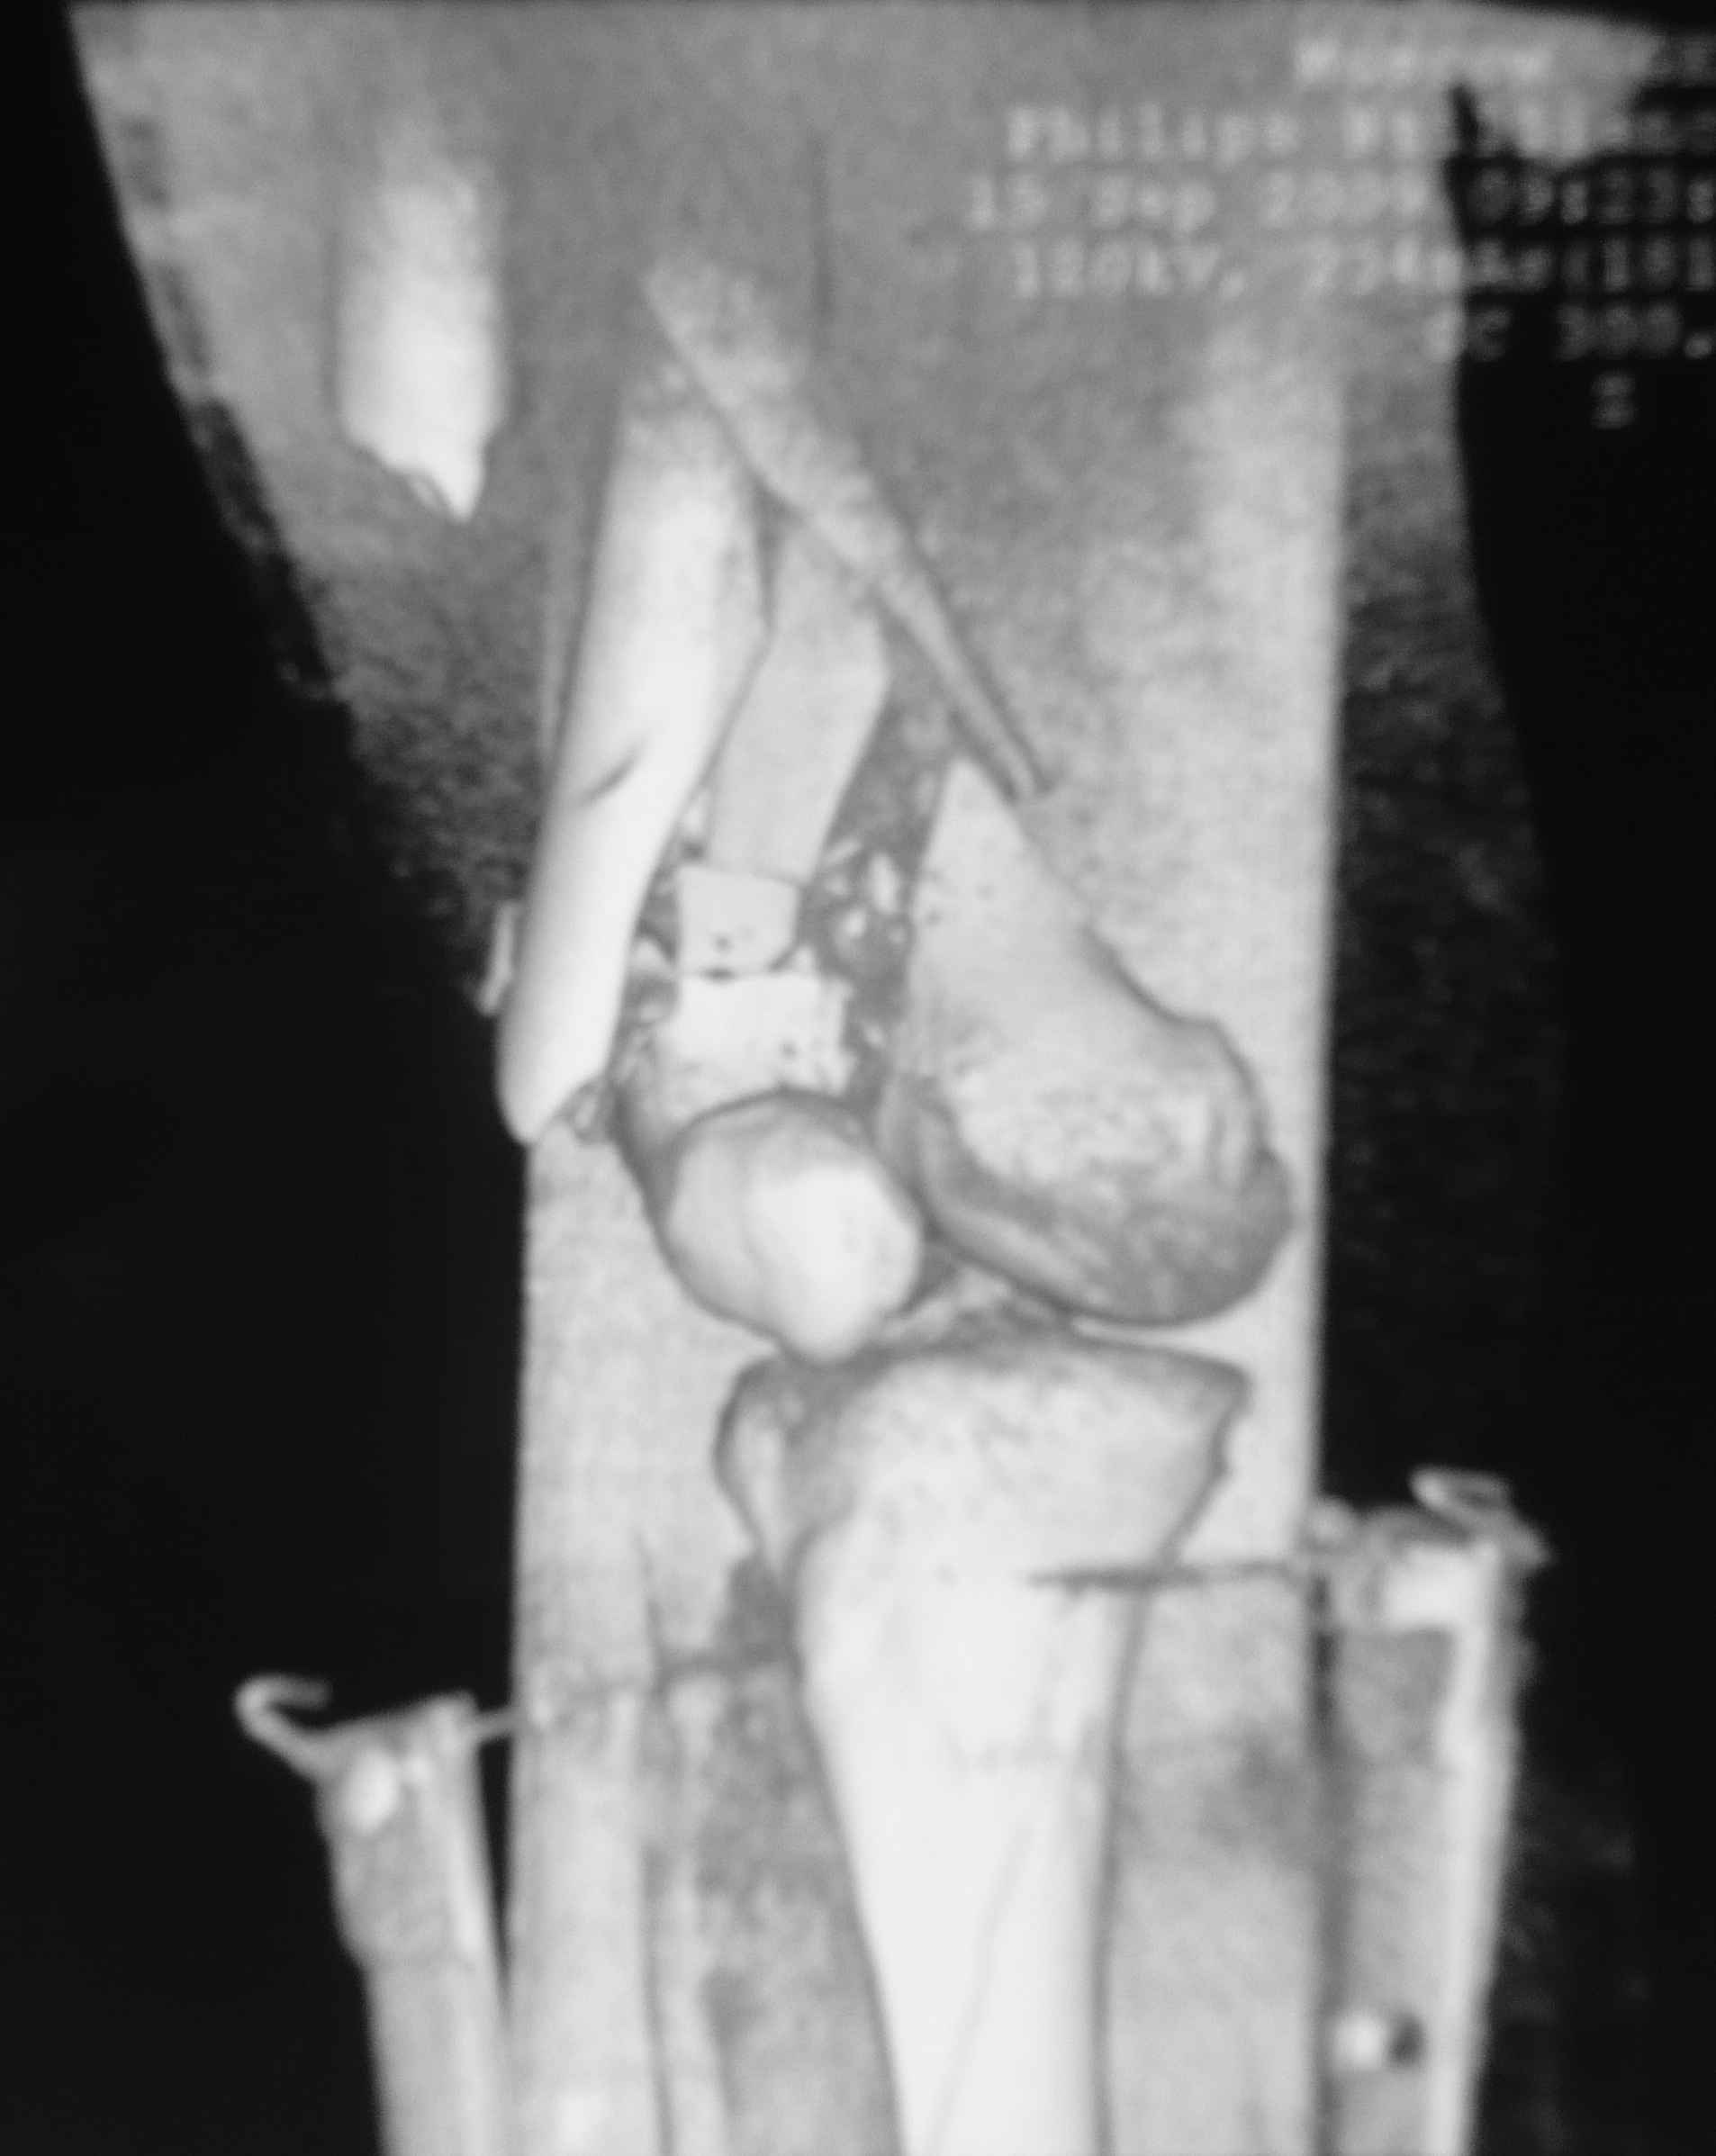

Это перелом не нижней трети, а дистального суставного конца, с распространением на диафиз. Что-то между C2 и C3. Но пока ближе к C2 по увиденному - вторую проекцию еще не показали.

На профиле стало видно, что открываться придется, это перелом C3, хотя можно назвать и C2+, т.е. с еще и фронтальным раскалыванием одного мыщелка. Надо сделать медиальную артротомию, ступеньку на внутреннем мыщелке устранить, ввести либо несколько временных спиц спереди назад, или сразу винт вдоль эллипса мыщелка. А дальше как выше написано - дистрактор, и штифтовать. Учитывая наличие открытого колена - вполне уместно ретроградно.

еще кт

я совсем молодой доктор так что без обид могу ошибаться во многом.